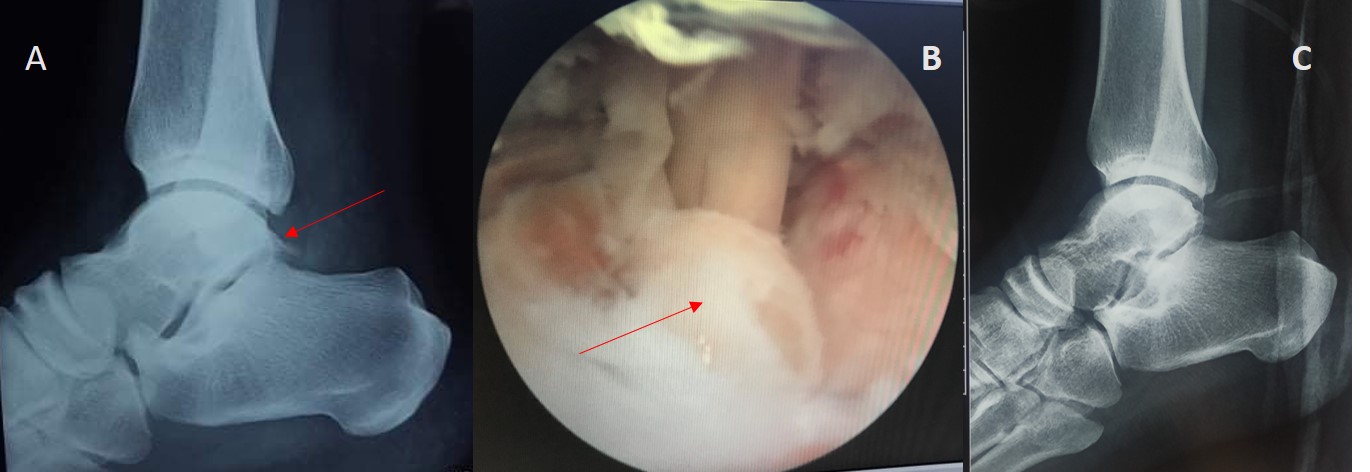

Hình 1: Bệnh nhân Nam 28 tuổi

A & B: Khối gai xương sau xương sên trên X quang trước mổ và hình ảnh nội soi trong mổ (mũi tên đỏ)

C: Hình ảnh tổn thương viêm gân gấp ngón cái dài trong mổ

Hình ảnh sau mổ trên X quang và vết mổ